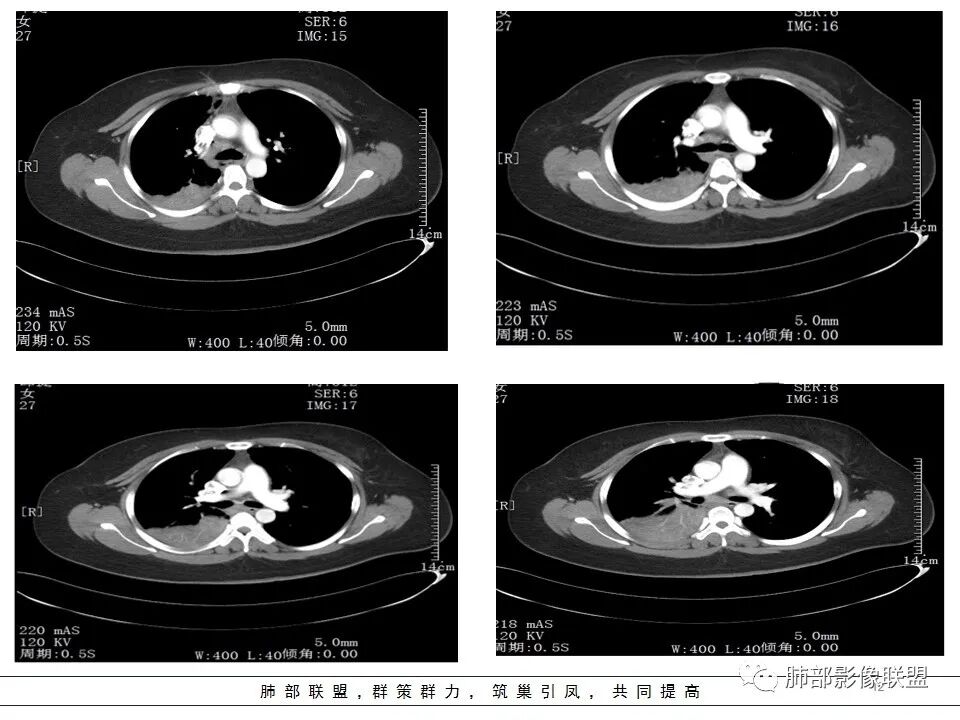

纵隔淋巴结肿大,以2/4R区、3区为主

这里不知道是不是内乳的淋巴结?

如果是内乳淋巴结,代表淋巴瘤

我再捋一捋支气管

右主支气管

上叶支气管

中间段

争议的地方这是上叶?中叶?

关键点——中间段支气管堵塞处

其实关键点在中间段支气管

通过视频显示中间段堵了

支气管腔内占位

远端低强化,提示粘液很多

纵隔淋巴结大